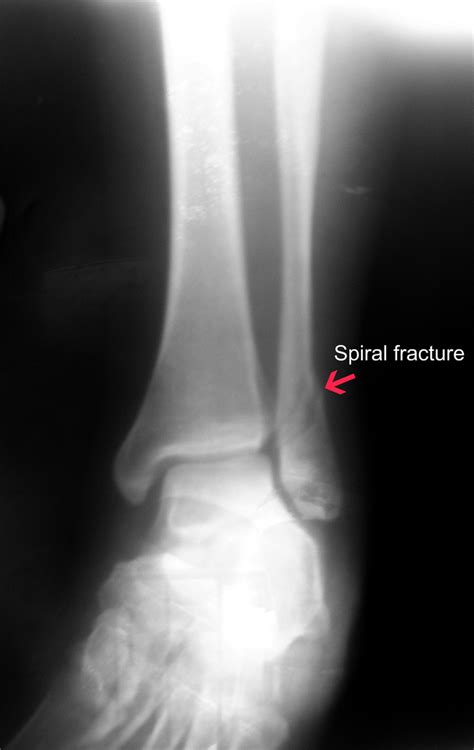

A spiral fracture occurs when a twisting force is applied to the bone, causing a diagonally winding break around the shaft. Unlike transverse or comminuted fractures, the spiral pattern results from rotational stress, commonly seen in sports injuries, military accidents, or falls with rotational momentum. Because of its angular break line, spiral fractures can be deceptively stable at first glance but often carry hidden risks.

Many people mistakenly believe that if a fracture feels “stable” or the crack looks small, the bone can fuse without medical intervention. The truth is, spiral fractures rarely heal properly through rest alone. Due to the twisting trauma, blood vessels within the bone may be severely damaged, and the bone fragments often misalign—preventing natural healing without proper realignment (reduction) and immobilization. Unlike simple cracks, spiral fractures frequently require surgical stabilization to restore proper alignment and prevent long-term joint dysfunction.